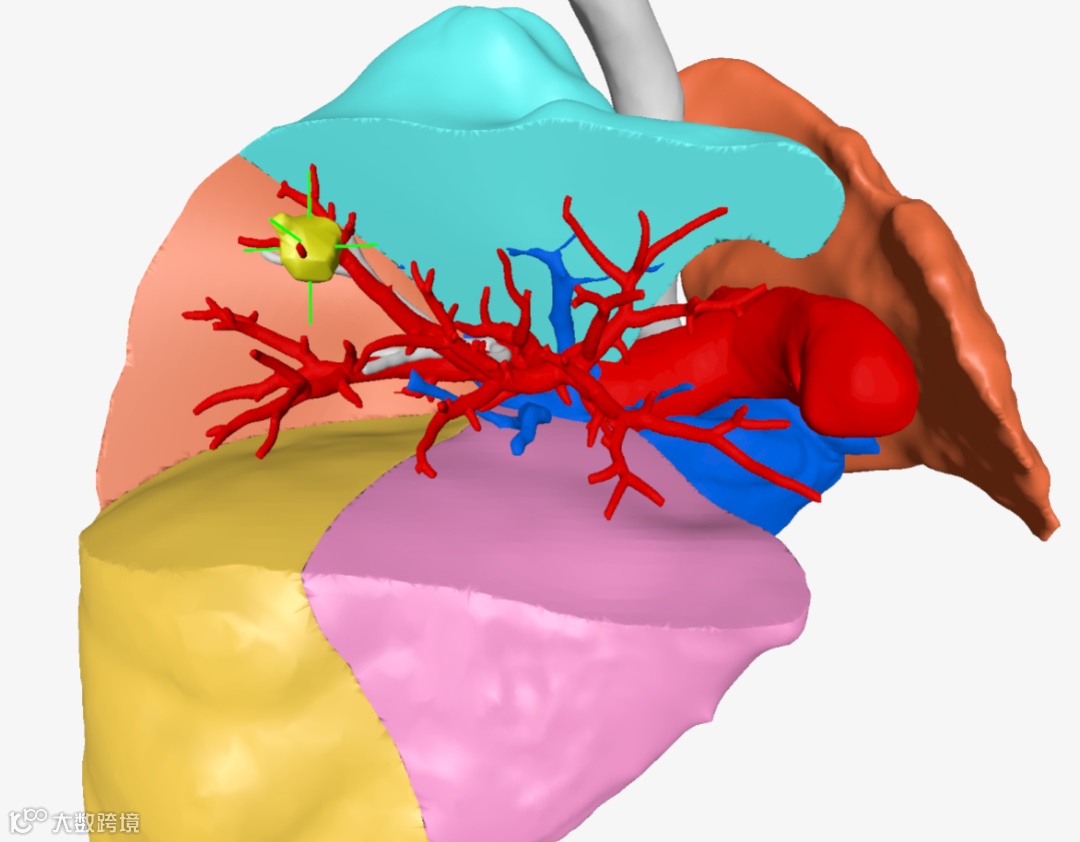

▲▲▲三维重建肺叶肺段

该院胸外科手术团队用瀚依科技的AI三维重建服务,真实还原了结节的大小、位置和深度,全方位、多维度地观察了患者结节的空间位置、结节与周遭脏器粘连程度、结节对血管的侵占情况,并对手术需要的重要信息进行精准定量分析。

▲▲▲病变与肺叶之间关系

▲▲▲病变与肺段之间关系